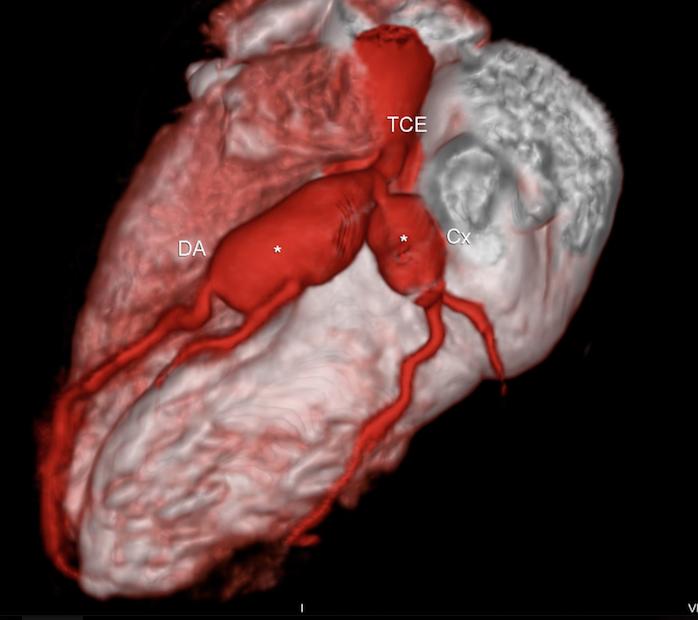

Ja vimos a importância teórica do reconhecimento das características das placa ateroscleróticas pela angiotomografia coronariana, uma vez que esse é o único método não invasivo que pode fornecer essa …

15 MARÇO 2019